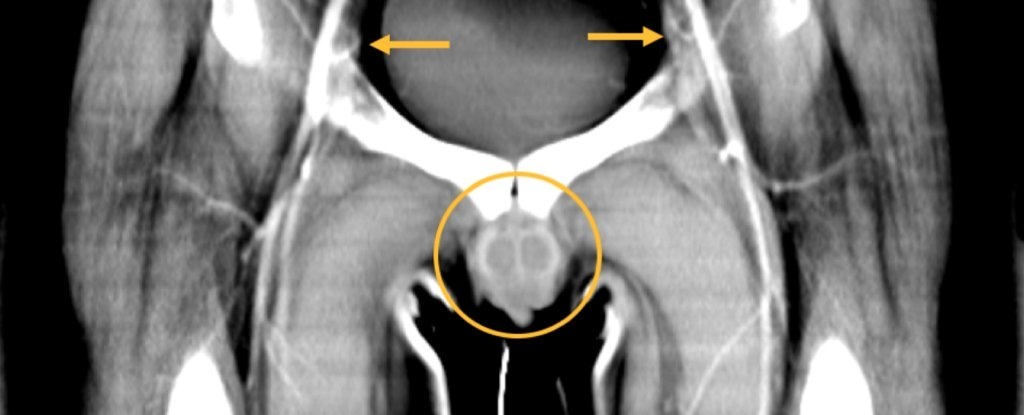

| Chiến tranh đã cướp đi gần như hoàn toàn phần thân dưới của người cựu chiến binh, bao gồm dương vật, bìu và hai chân. Ảnh: NEJM. |